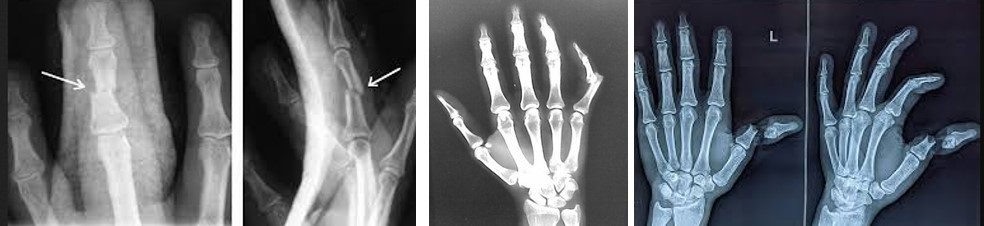

Застаріла травма сухожилка розгинача пальця на рівні дистальної фаланги. Результат консервативного лікування.

Для виключення переломів фаланг пальців та відриву кісткового фрагменту разом з сухожилком, застосовують рентгенографію у двох проекціях. Чому саме рентгенографія є першим методом діагностики?

Переломи кісток кисті – поширена травма. На частку переломів кісток кисті припадає близько 35% всіх травматичних пошкоджень кісткової системи. Зазвичай причиною перелому кісток кисті стає удар по кисті або падіння з упором на кисть, також причиною є виробничі травми – попадання пальців чи кисті в промислові агрегати. Переломи кісток кисті включають переломи зап’ястя, п’ясткових кісток та фаланг пальців. (с)